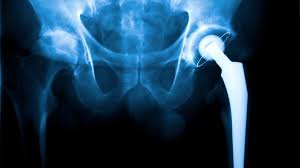

Hip pain and stiffness can slowly take over daily life. People end up avoiding movement, which ultimately reduces quality of living. When conservative treatment fails, robotic hip replacement often becomes the best solution. In Betul, Dr. Utsav Agrawal is recognized as the best robotic hip surgeon at Varunam Super Speciality Hospital. He combines advanced surgical expertise with robotic technology to deliver precise joint replacement and faster recovery.

Before surgery, Dr. Agrawal reviews imaging studies and creates a 3D surgical plan. Then, with robotic assistance, he performs precise bone preparation and implant positioning. The robot enhances his accuracy, while he retains full surgical control. Because of this teamwork, patients experience improved joint alignment and better long‑term stability.

During surgery, the robotic system helps map bone contours and joint alignment. At all times, Dr. Agrawal remains in control, making real‑time decisions that match the patient’s goals. After surgery, patients receive structured care including pain management and physiotherapy. Early mobilization under guided exercises helps restore strength and walking ability quickly.